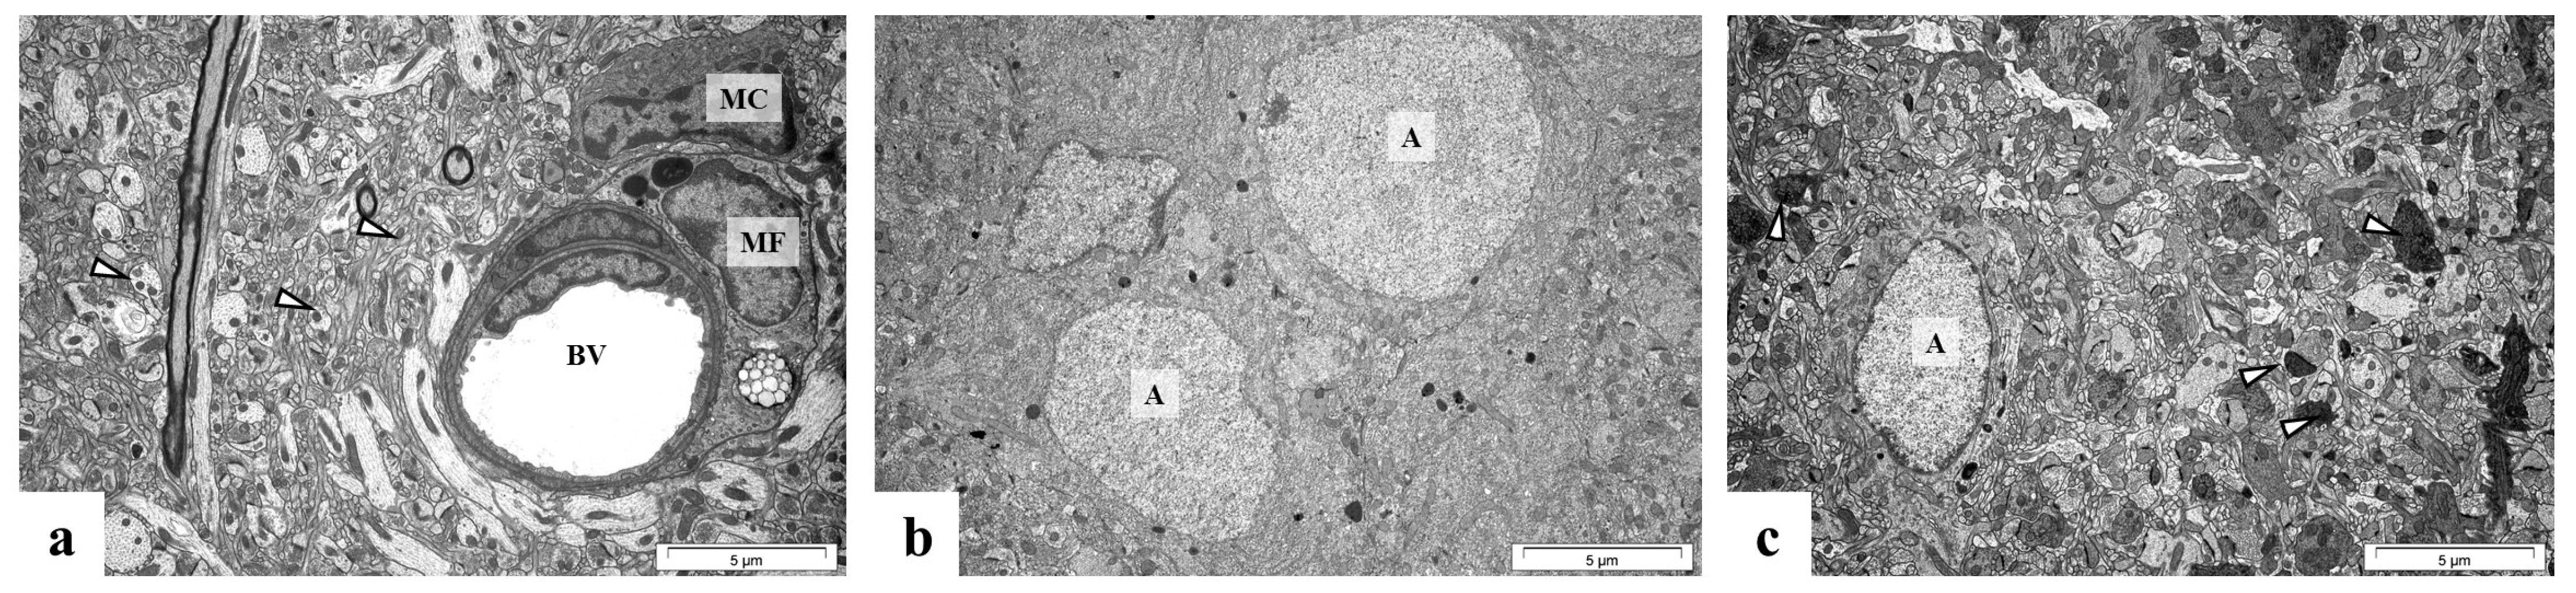

2.5. Perinatal Exposure to Pb Causes Ultrastructural Changes in the Glial Cells in the Brain of Adult Rats